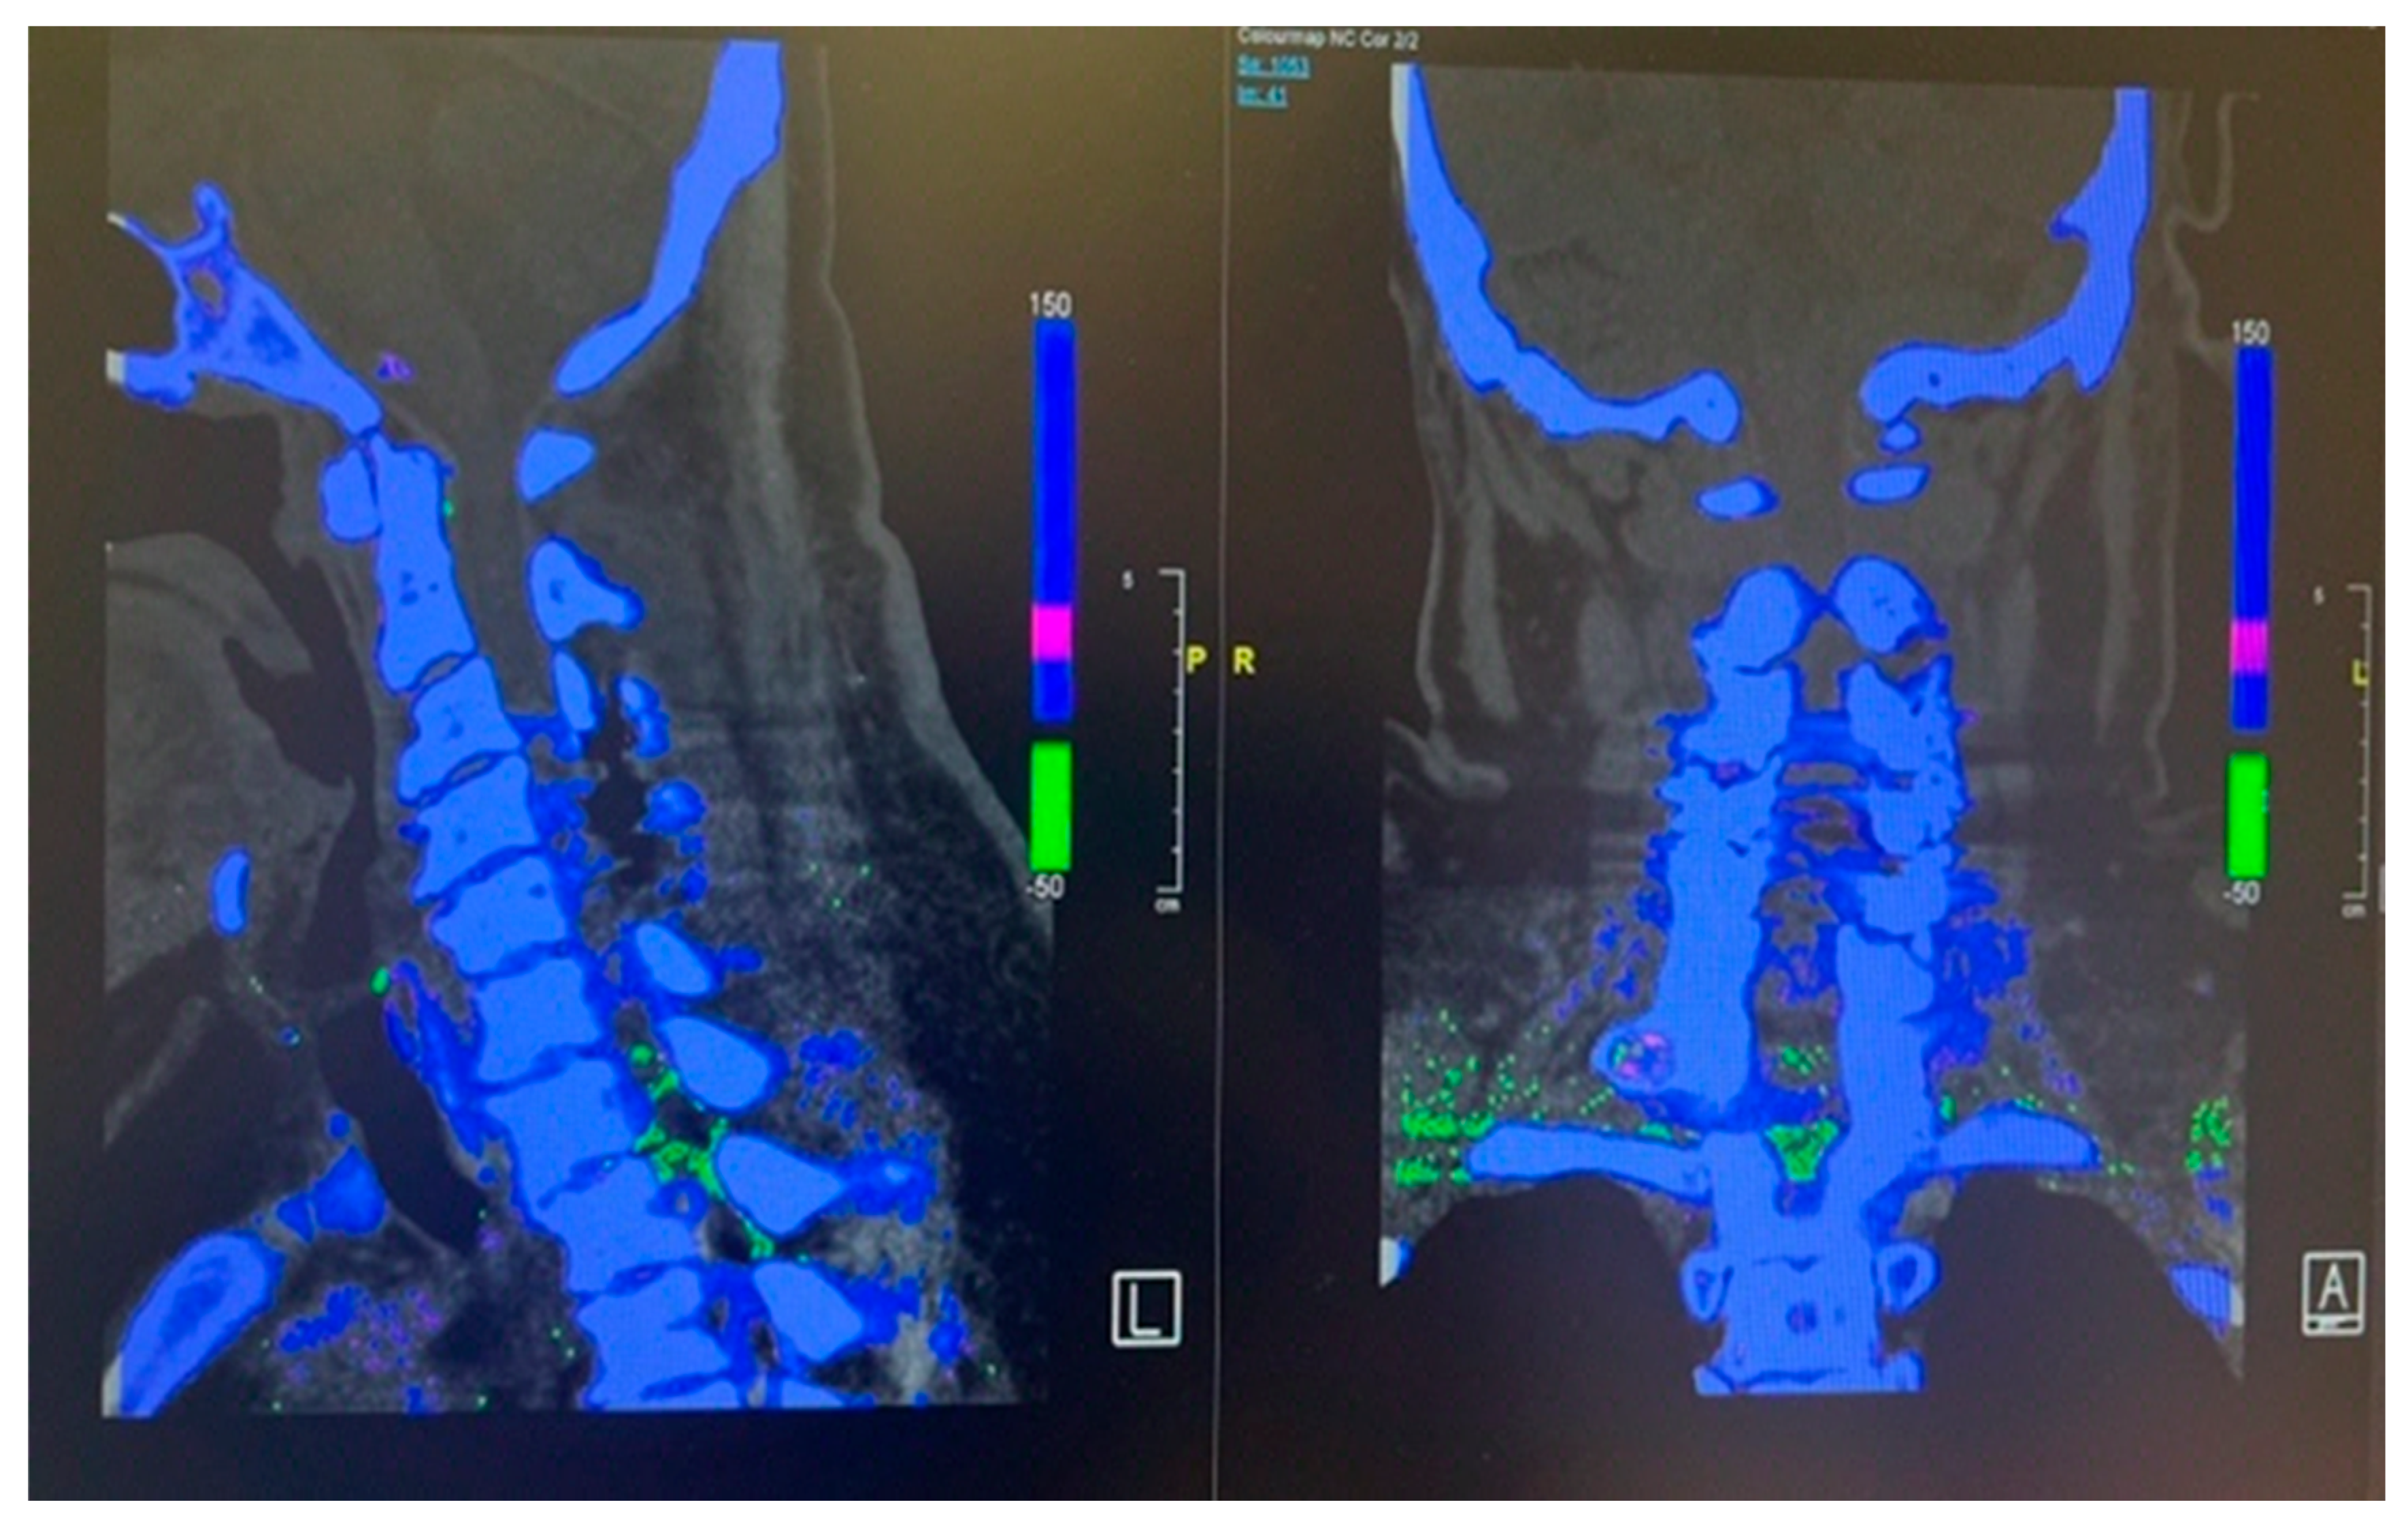

Inflammatory markers showed raised CRP level of 292. Meanwhile Hip and Knee team advised X Rays both knees reported as bilateral osteoarthritis with bilateral moderate to large suprapatellar effusion. Later on, they did bilateral knee joints aspiration and sent aspirate for laboratory evaluation which showed raised nucleated cells (35415), neutrophils (92%) and negatively birefringent crystals Based on knee joint aspiration result the patient was referred to Rheumatology for further assessment and serum Uric acid was sent as per their suggestion showed raised level of 532. Patient was counselled for image guided biopsy of the reported levels on MRI spine in order to exclude infective spondylodiscitis and septic arthritis but due to patient reluctance it was not done. While keeping in mind the patient clinical, radiological and lab tests picture dual energy CT whole spine was done reported as Urate deposits at the T10/11 and lower lumbar discs especially at L5/S1. Green pixelation in the rest of the thoracolumbar spine appears to represent artifact rather than further urate deposits. In particular, there does not appear to be urate deposits at the region of right the right T11/12 facet joint as shown in the Figure 7 (A) and (B). In order to start a definitive treatment, image guided biopsy was discussed with the patient but not done due to patient reluctance. Meanwhile multidisciplinary meeting was held between Infectious disease and Rheumatology teams while keeping in mind the differential diagnosis and a conclusion was made to treat the patient for Gout. Rheumatology team started the patient on 3 weeks tapering dose of prednisolone followed by 5 mg OD dose for few months for Gout prophylaxis. He was also started on Allopurinol an anti-Gout medication with a dose of 50 mg OD. Later on, Patient was transferred under the care of rehabilitation team. Patient CRP and serum Uric acid were trended over the time and showed progressive declined in their levels along with clinical improvement. Follow up MRI lumbar and thoracic spine revealed improvement in the form of slight signals improvement at L5/S1 shown in Figure 5 (B) and disappearance of right T10/11 facet cyst shown in the Figure 8 (B). After completing rehabilitation, the patient was discharged to the home with the follow up schedule with different concerned specialties.

Figure 7. Dual energy CT of whole spine sagittal view (A) and coronal view (B) showing Urate crystal deposits at the levels of T10/11 and L5/S1. The rest of the green pixelation is an artifact rather than urate crystals.

Literature review of spinal gout cases shows that the most common laboratory tests finding is increased uric acid level in the blood having level more than 7 mg/dl which is the cut off value for the definition of hyperuricemia. Most of the radiological findings on the plain x rays and MRI spine are variable and nonspecific. MRI of tophaceous gout mostly shows low to intermediate intensity of T1 weighted sequence while T2 weighted images are highly variable ranging from homogenous low to homogenous high intensity. MRI spine with contrast varies from homogenous to peripheral heterogenous enhancement. Because of the variable and nonspecific radiological picture of MRI it is difficult to differentiate from the other mass occupying lesions in the spinal cord. The most helpful radiological investigation is dual energy CT scan which can differentiate it from other inflammatory mimicking conditions especially Rheumatoid arthritis which is considered as Calcium Phosphate deposition disease and the main reason is that it has two X rays’ tubes having with different peak kilovoltages (80 and 120 kVp) which can differentiate Urate crystals of Gout from Calcium Phosphate of Rheumatoid arthritis. The sensitivity and specificity of dual energy CT is for Mono Sodium Urate crystals is 90% and 83%, respectively. Other than dual energy CT scan cytological or histopathological studies can help to make a definitive diagnosis because of high sensitivity and specificity for urate crystal [13,17,18]. In our case series the level of blood uric acid level was considerably high values having 445 mg/dl in the first case and 552 mg /dl in the second case consisted with statement mentioned before. Similarly, we did dual energy CT scan in both cases gave more definitive clue of Gout involvement of the targeted locations in spine which were detected by prior MRI images. The limitations in our study are that we were unable to perform the histological examination of the sample taken during the surgery because in first case of cervical spine we took sample for histological examination during the surgery but the sample was sent in Formalin due to which crystal examination was unable to perform while the 2nd case was managed conservatively with subsequent resolution of Thoracic spine facet joint cyst with anti-gout medications reported in follow up MRI spine. Based on these limitations it is suggested that the tissues samples should be sent in normal saline in spite of fixing in Formalin.